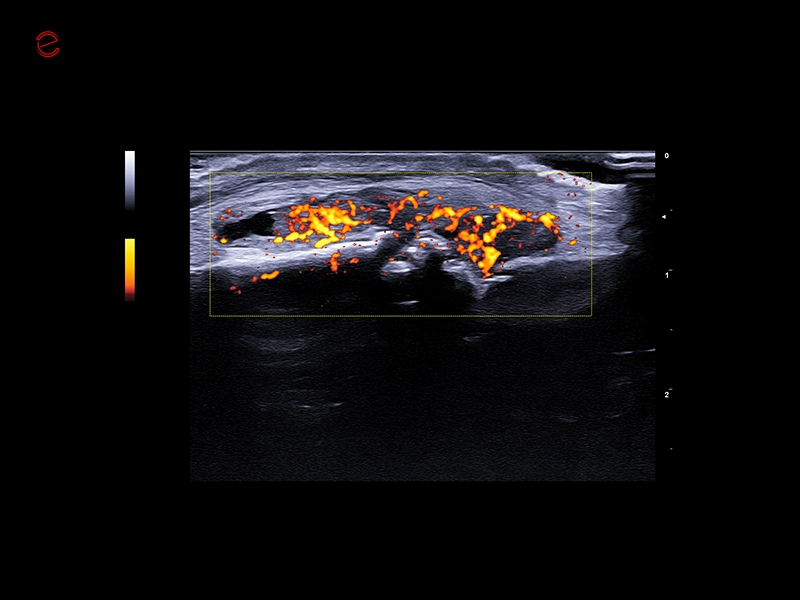

MyLab™9 Platform - MSK BodyMap and real-time XFlow on X-Ray extremities

MyLab™9 Platform - MSK BodyMap and real-time XFlow on X-Ray extremities